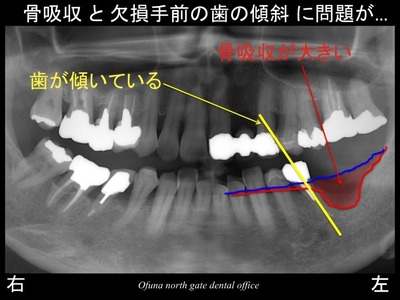

いつものように 骨吸収の状態を分かりやすくするために

骨吸収の状態を線で書いたのが以下のレントゲンになります。

青線が骨吸収を起こす前の骨の位置です。

赤線は、現在の骨の位置です。

かなりの骨吸収が起こっているのが分かるかと思います。

さらに わかりやすくするために、

骨吸収部位を赤色で表示します。

骨吸収が本当に大きいことが分かります。

骨吸収以外にも問題があります。

欠損部手前の歯が斜めになっているのです。

これが欠損部にインプラント治療を行うのに問題となっています。